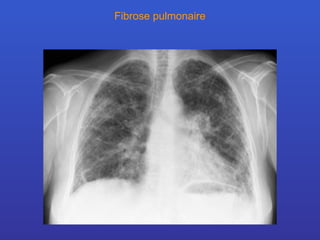

Fibrose pulmonaire